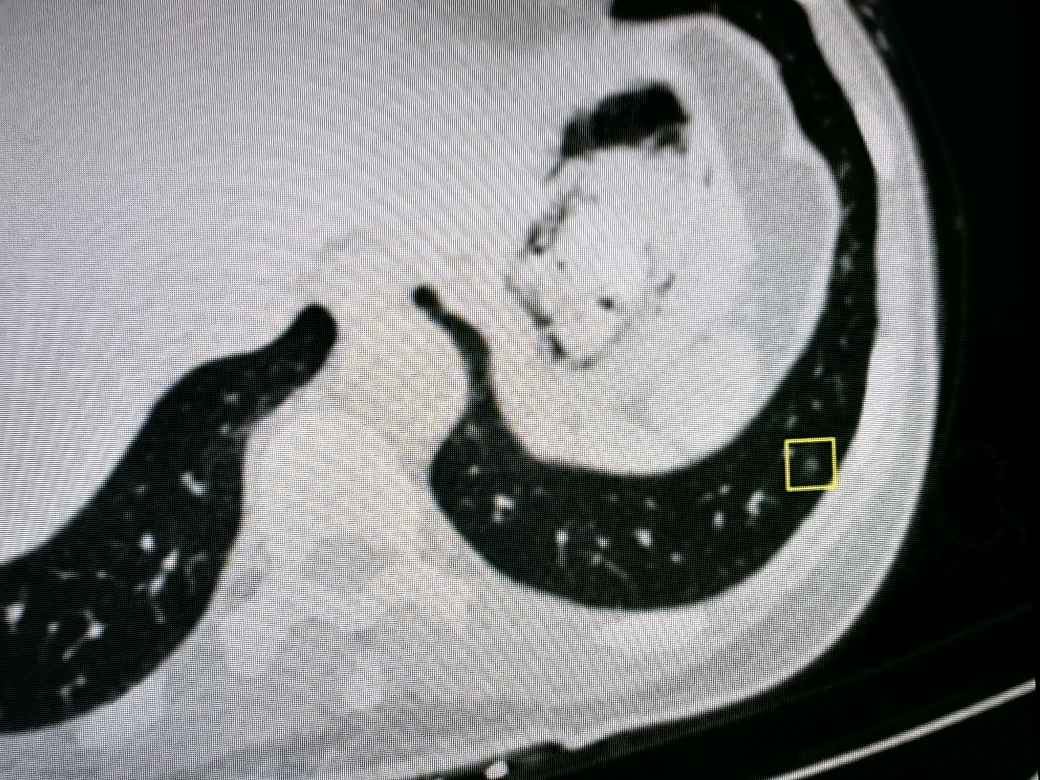

第四种情况:钙化灶

您可以把钙化理解为病灶内部出现了类似石头质地的钙质沉积。这是机体将陈旧病灶包裹、隔离的一种自我保护机制,如同给一个不再活跃的病灶“封存”起来。这种情况很少有恶性的情况。